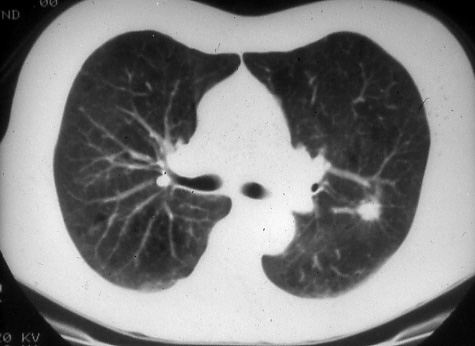

LUNG

CANCER

A Handbook for Staging, Imaging, and Lymph Node Classification